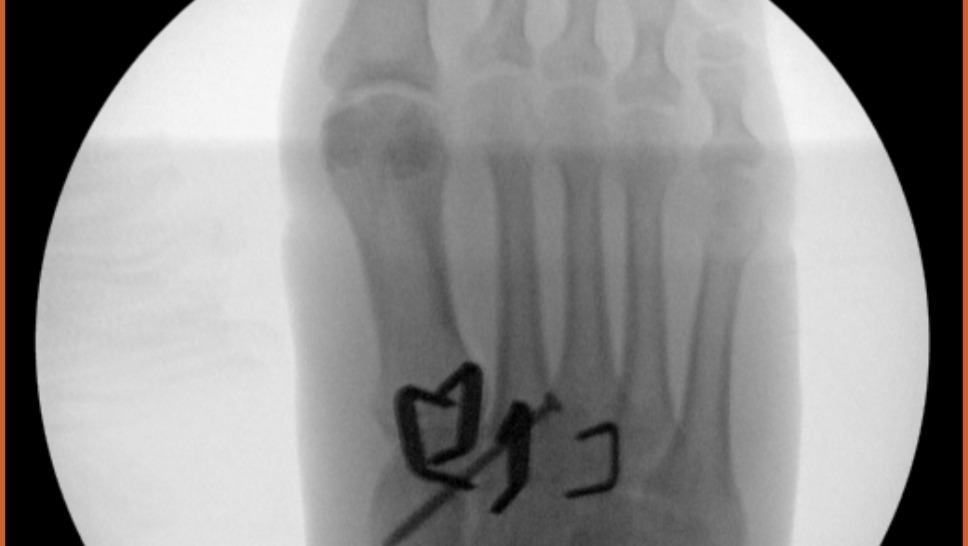

On 6/30 I was in a motorcycle accident. In the middle of a (amicable) divorce, I did something for me and it backfired; I traded some stuff for my first motorcycle. A low-speed fall on my first ride, the foot peg dug into my foot and scrambled my bones. Four out of five metatarsals were dislocated and a midfoot bone was crushed. $121K worth of surgery later, including a bone graft and several pieces of metal in my foot along with a screw, I'm in recovery.